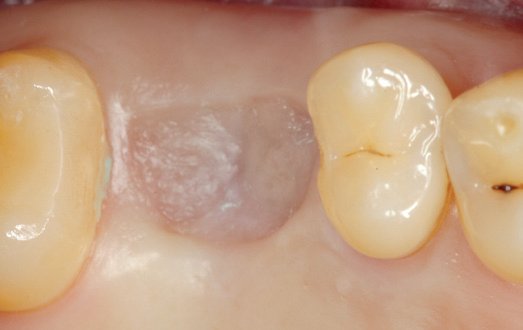

03/10 - Presentation of the soft tissue situation before implantationInternal sinus lift with maxresorb® inject - case Dr. Frank Kistler

-